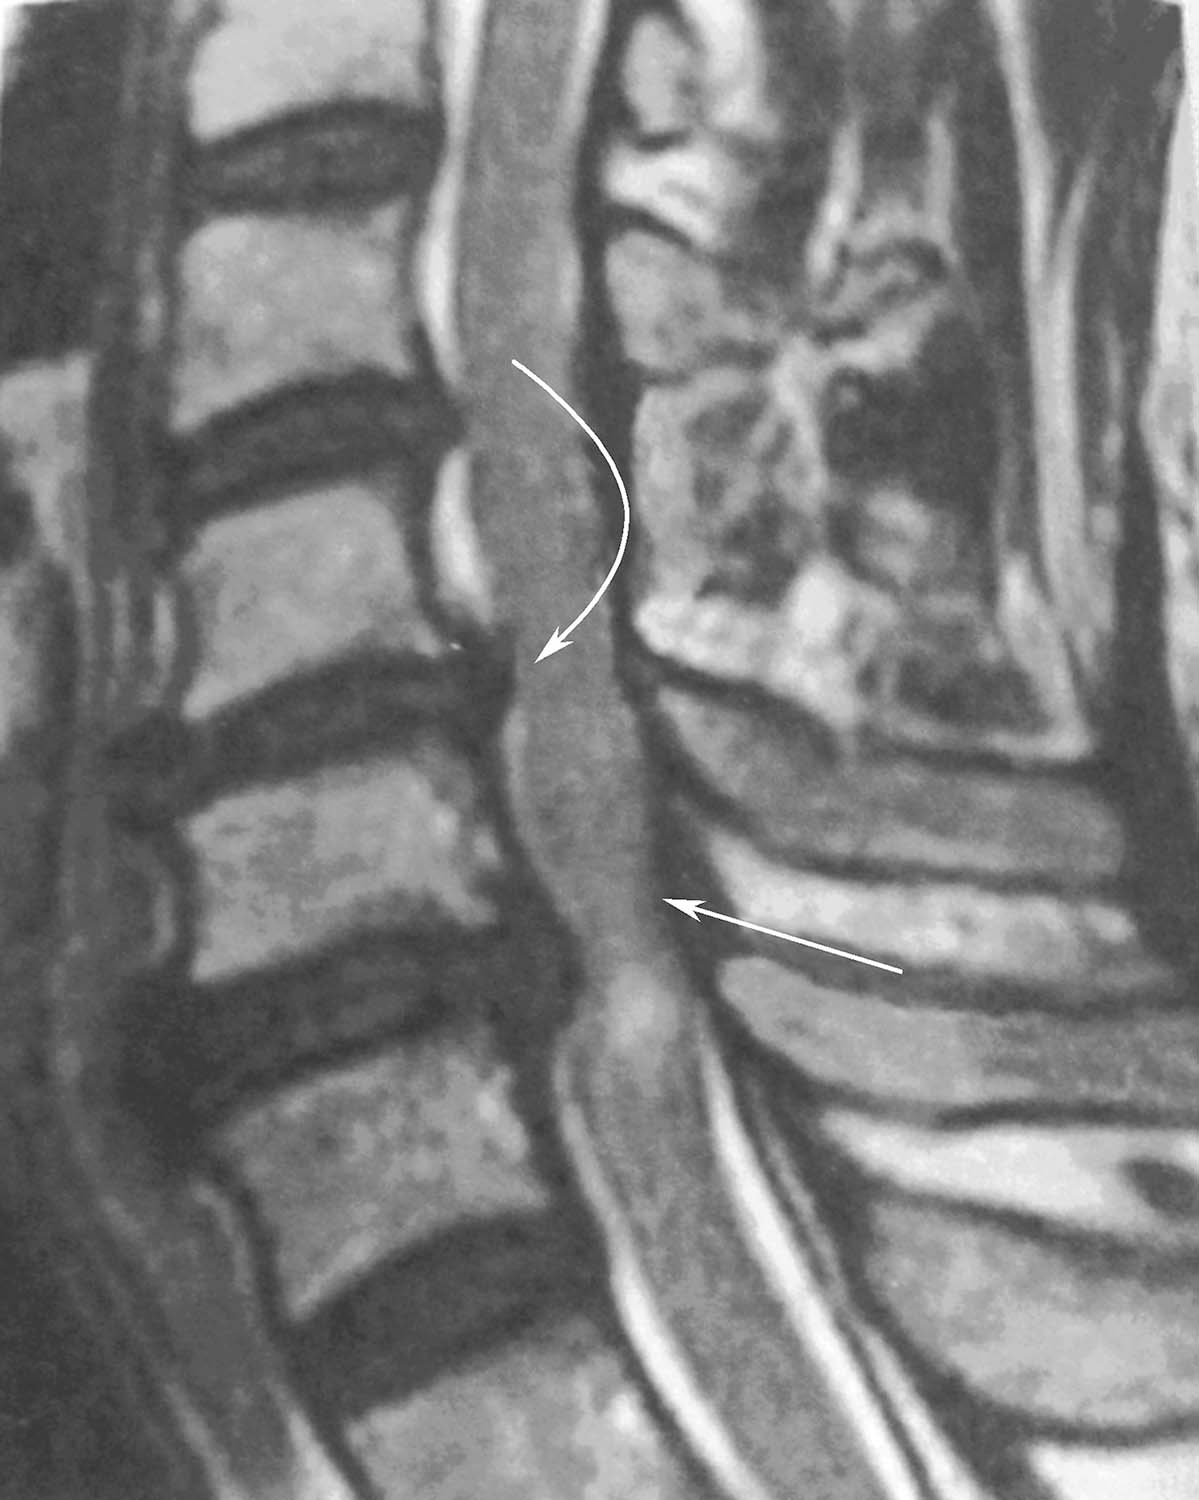

髓核突破纤维环和后纵韧带,突出部分与盘内髓核尚有一蒂相连。只突破前者为后纵韧带下型,同时突破后者为后纵韧带后型。

图16-1-3 椎间盘突出、脱出图示弯箭为突出,直箭为脱出